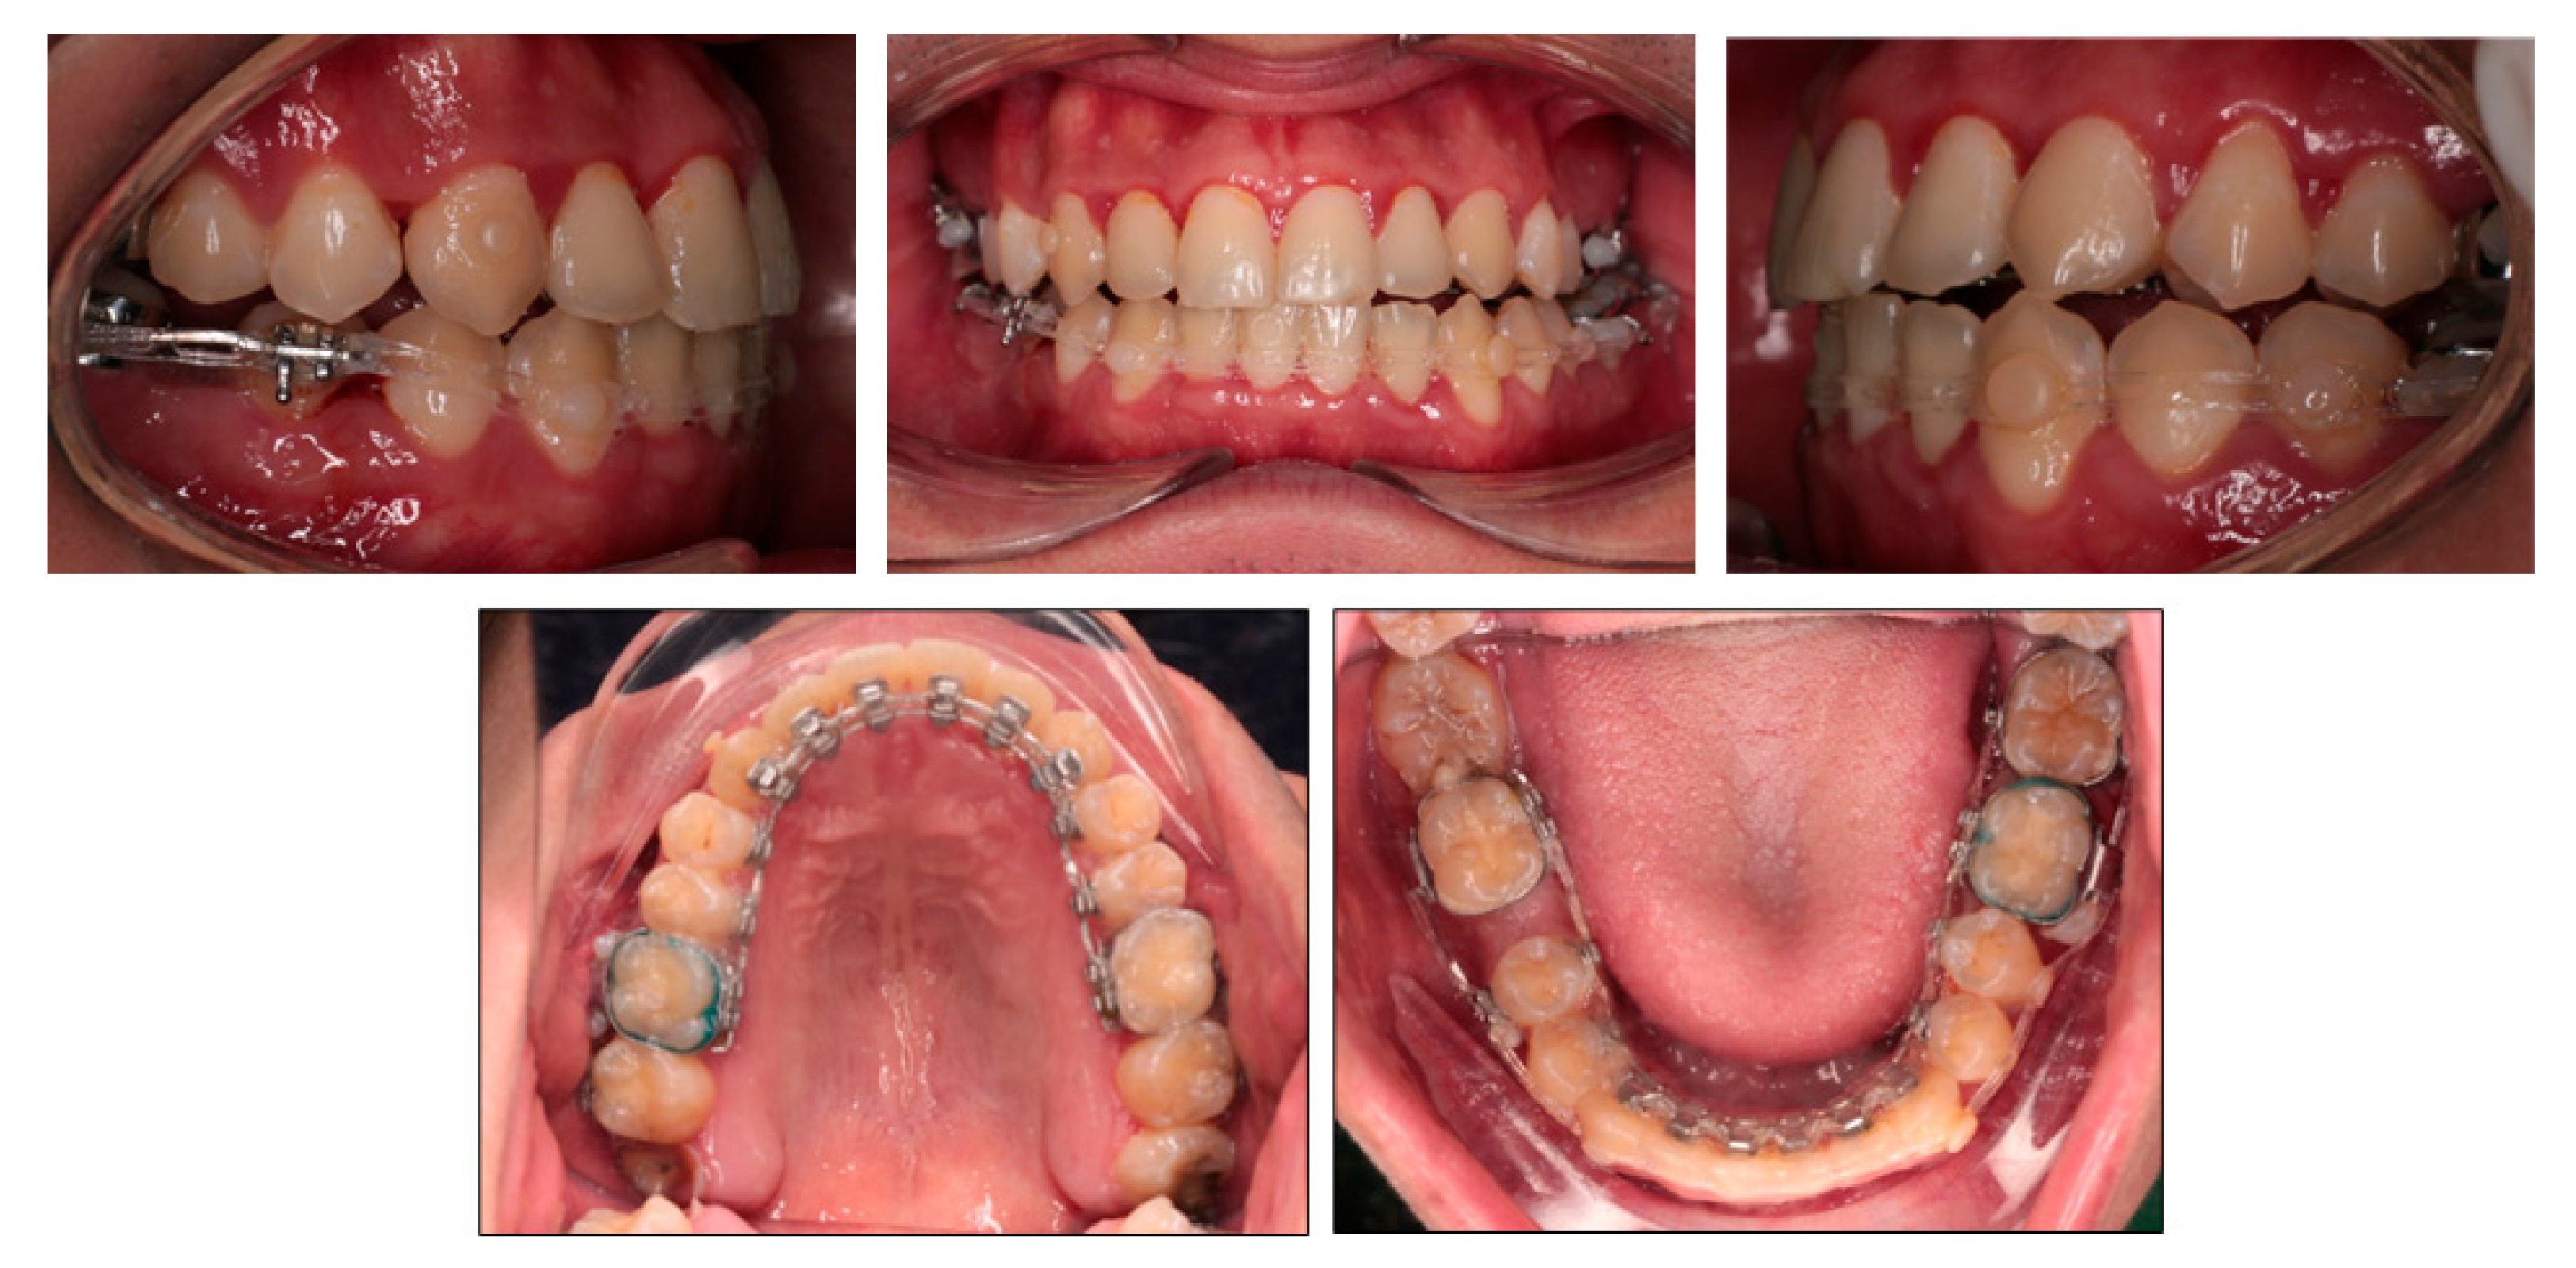

2.1. Diagnosis and Etiology

2.4. Treatment Plan

2.5. Treatment Progress